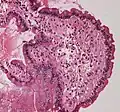

Diagnosis of amyloidosis generally requires tissue biopsy. The biopsy is assessed for evidence of characteristic amyloid deposits. The tissue is treated with various stains. The most useful stain in the diagnosis of amyloid is Congo red, which, combined with polarized light, makes the amyloid proteins appear apple-green on microscopy. Also, thioflavin T stain may be used.[11] A number of imaging techniques such as a DPD scan or SAP scan are also in use.[12]

Tissue can come from any involved organ, but in systemic disease the first-line site of the biopsy is subcutaneous abdominal fat, known as a "fat pad biopsy", due to its ease of acquisition versus biopsy of the rectum, salivary gland or internal organs. An abdominal fat biopsy is not completely sensitive, and sometimes, biopsy of an involved organ (such as the kidney) is required to achieve a diagnosis.[11] For example, in AL amyloidosis only 85% of people will have a positive fatpad biopsy using Congo red stain.[6] By comparison, rectal biopsy has sensitivity of 74–94%.[7]

Small bowel duodenum with amyloid deposition Congo red 10X

Small bowel duodenum with amyloid deposition Congo red 10X Amyloidosis, dystrophic calcification

Amyloidosis, dystrophic calcification Small bowel duodenum with amyloid deposition 20X

Small bowel duodenum with amyloid deposition 20X Amyloidosis, Node, Congo Red

Amyloidosis, Node, Congo Red Amyloidosis, blood vessels, H&E

Amyloidosis, blood vessels, H&E Amyloidosis, lymph node, H&E

Amyloidosis, lymph node, H&E Amyloidosis, lymph node, polarizer

Amyloidosis, lymph node, polarizer Cardiac amyloidosis. H&E stain.

Cardiac amyloidosis. H&E stain. Micrograph showing amyloid deposition (red fluffy material) in the heart (cardiac amyloidosis). Congo red stain.

Micrograph showing amyloid deposition (red fluffy material) in the heart (cardiac amyloidosis). Congo red stain.